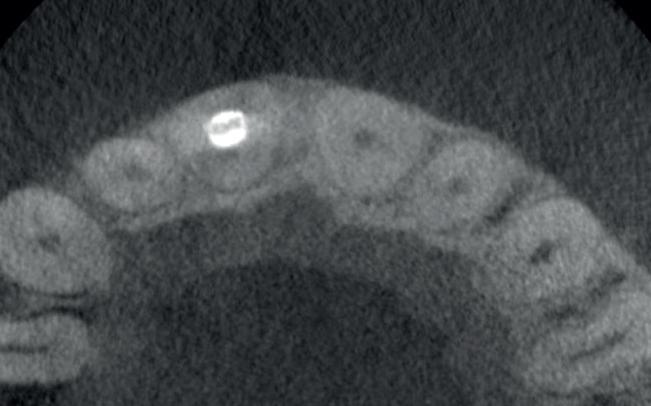

2. Occlusale opname onderfront: standswijzigingen bij de 32 en de

31 door een geactiveerde retentie draad.